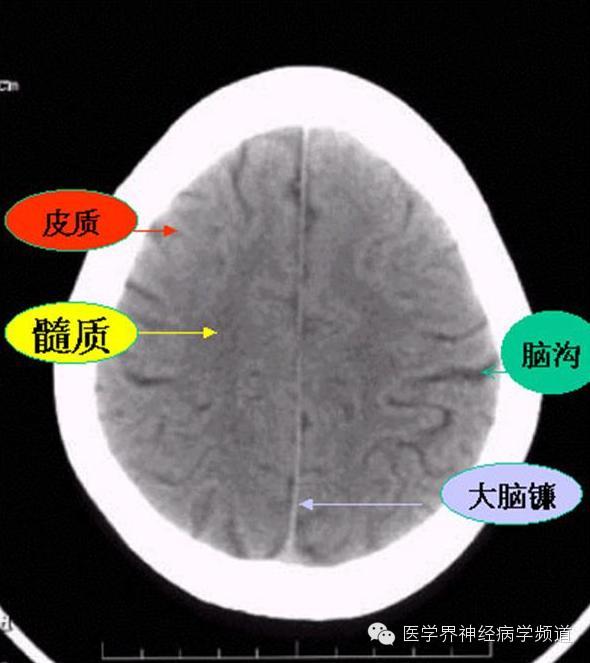

神经影像CT读片step by step